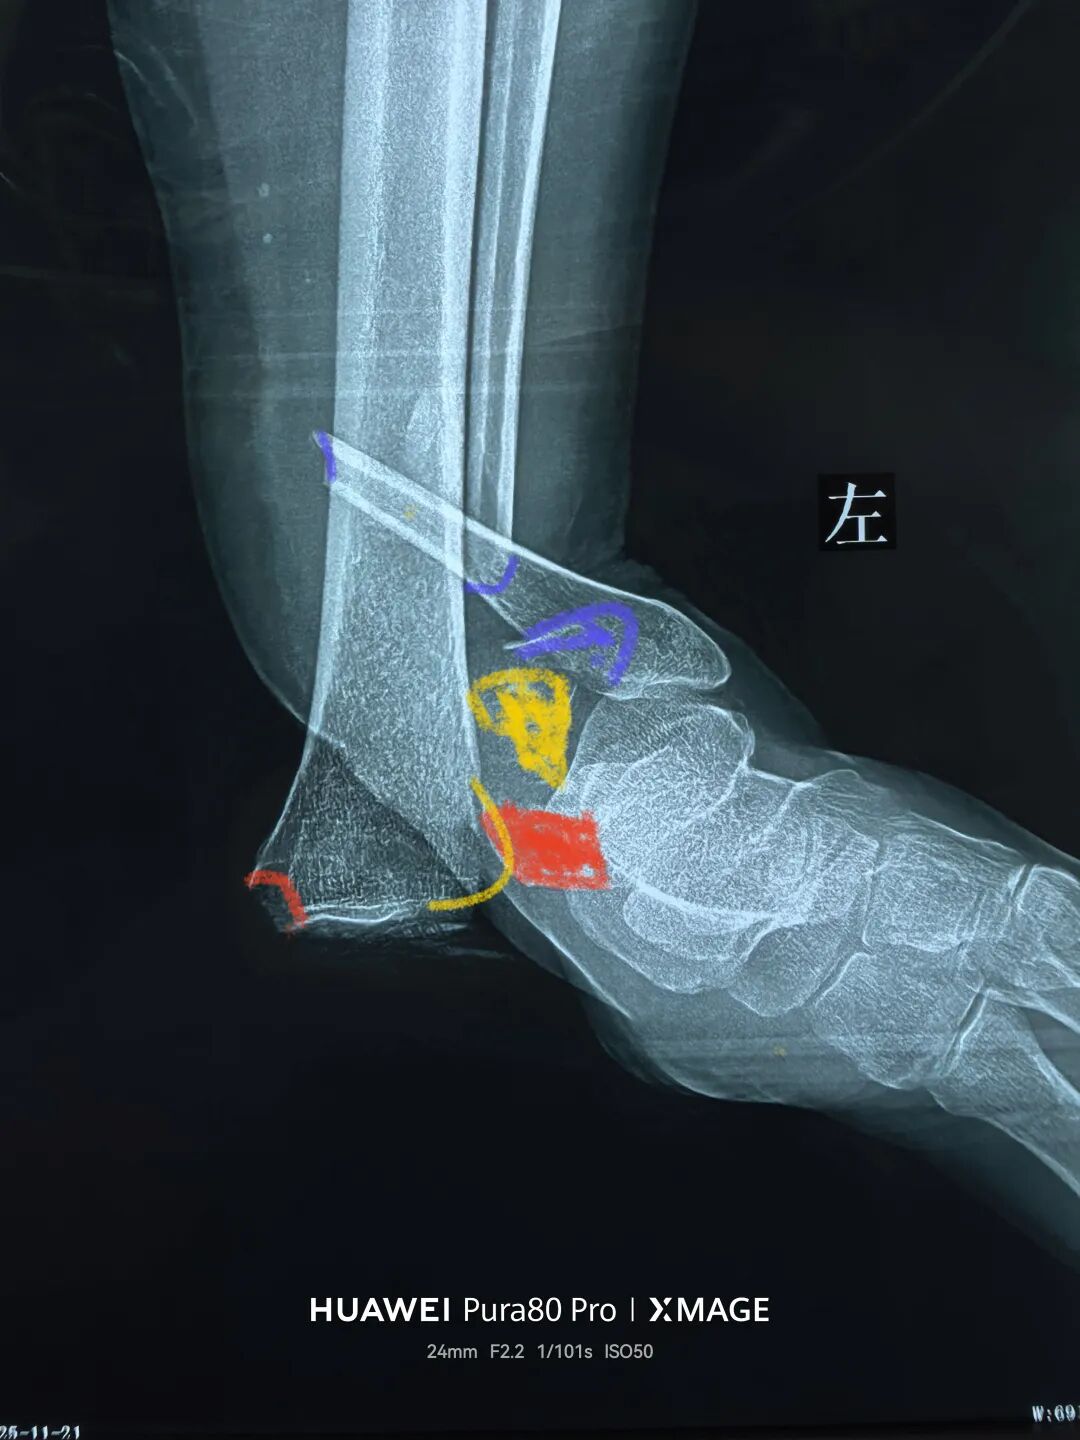

3,复位后踝

后踝有曲折

图片

没有松外架

骨折没复位

松外架后,保持踝关节中立位

依靠软组织铰链复位后踝